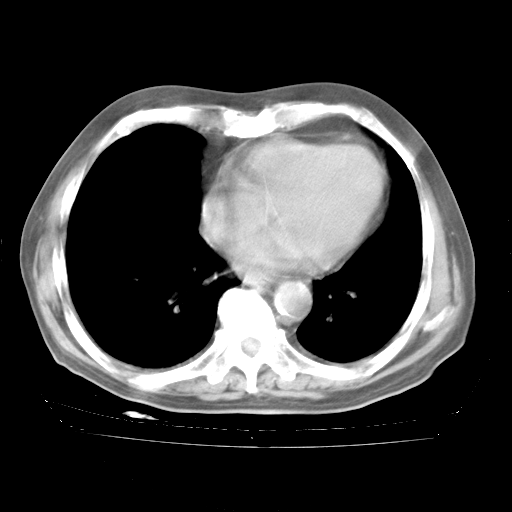

4月28日肺部CT——再次出现类似去年5月9日——透光度降低,“间质性”改变。